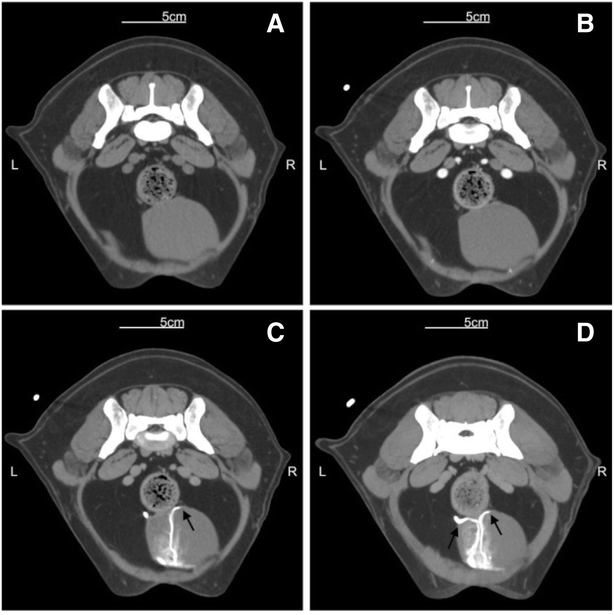

The uretero-vesicular junction, was easily identified in all (100 %) patients in the late bolus tracking scans, and clearly visualized when the MIP post-processing technique was adopted (Figs. 2 and 3).

Transverse images at the level of the uretero-vesicular junction. Gradual distribution of the contrast media: unhenhanced conventional scan (a), vascluar distribution in the enhanced conventional scan (b), late post-contrast enhanced series with bolus tracking technique (c), reconstructed by MIP (d). Black arrows indicate the uretero-vesicular junction